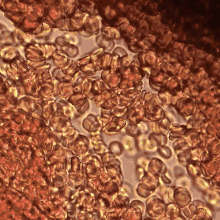

Erythrocytes aggregate in a special way, forming rouleaux. Rouleaux are stacks of erythrocytes which form because of the unique discoid shape of the cells in vertebrate body. The flat surface of the discoid RBCs give them a large surface area to make contact and stick to each other; thus, forming a rouleau. Rouleaux formation takes place only in suspensions of RBC containing high-molecular, fibrilar proteins or polymers in the suspending medium (often Dextran-2000 in-vitro). The most important protein causing rouleaux formation in plasma is fibrinogen. RBC suspended in simple salt solutions do not form rouleaux.[1][2][3]

Erythrocyte aggregation is a physiological phenomenon that takes places in normal blood under low-flow conditions or at stasis. The presence or increased concentrations of acute phase proteins, particularly fibrinogen, results in enhanced erythrocyte aggregation.

Current experimental and theoretical evidence supports the mechanism related to the depletion of high-molecular weight molecules (e.g., fibrinogen) for rouleaux formation.[4] This mechanism is also known as “chemiosmotic hypothesis” for aggregation.[5] Erythrocyte aggregation is determined by both suspending phase (blood plasma) and cellular properties. Surface properties of erythrocytes, such as surface charge density strongly influence the extent and time course of aggregation.